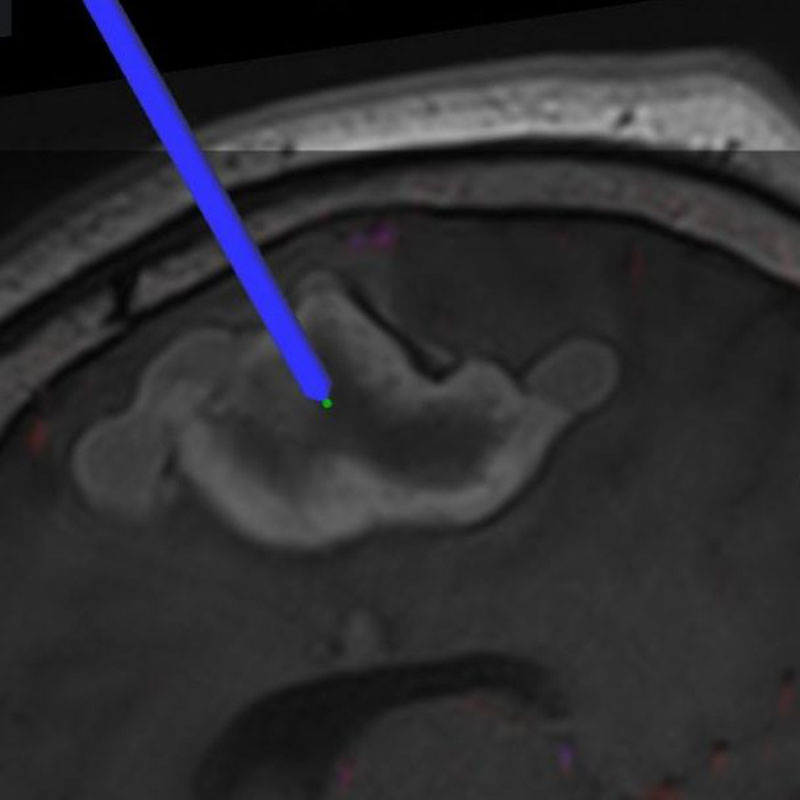

モニタリング

No.452 モニタリング

No.452 手術前

No.452 手術中